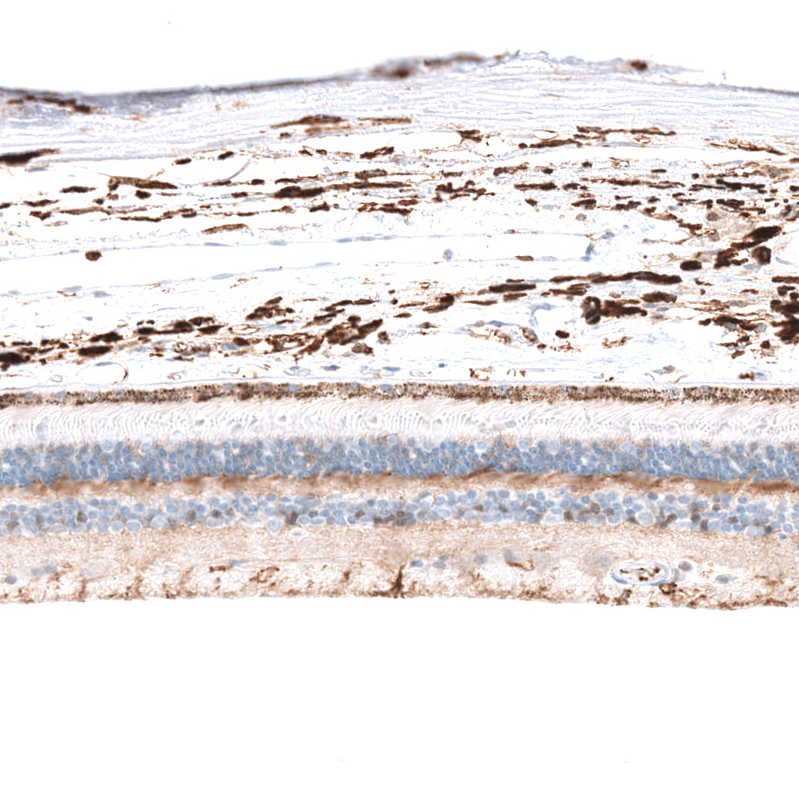

Immunohistochemical staining of human eye, retina shows moderate cytoplasmic positivity in outer nuclear layer and inner plexiform layer..

HPA016502

glycine receptor, alpha 1

Anti-GLRA1 Antibody

Polyclonal Antibody against HUMAN GLRA1